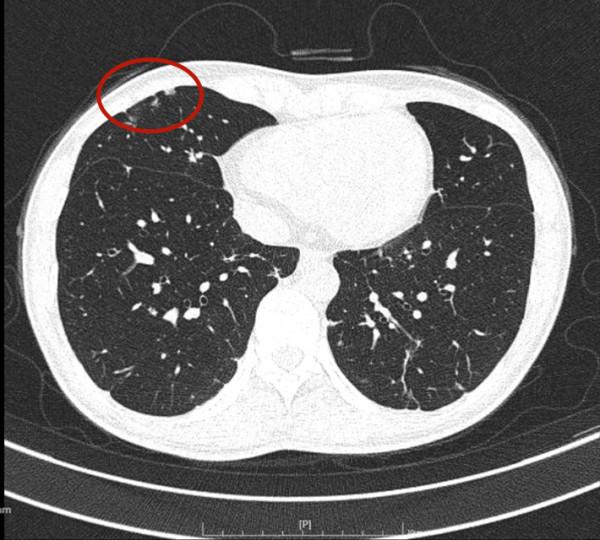

那麼多結節,基本上都是實性,分佈兩肺,形態不似圓形或類圓形的轉移瘤。是什麼呢?我們是不是一定要弄明白到底是什麼病?其實我覺得有時並不一定要弄清楚,所以我回復的意見如下:我認為我們看病,有時候可以從結果來反推,從而考慮是不是干預治療。比如這個病例的兩肺多髮結節,我看沒有一個是主病灶,也就是說“明顯考慮惡性的,其他考慮是這個病灶轉移的”這種樣子。那麼這些實性小結節,可能是:1、良性結節:包括慢性炎,纖維增生、肺內淋巴結、風溼結節、肉芽腫、隱球菌等各種可能性。但只要是良性,不處理不影響生命,也沒什麼不舒服,只需關注著,定期複查就可以了;2、腫瘤多發轉移:不管原發灶在哪裡,如果兩肺這麼多轉移,你再怎麼治療,預後也不好,現在還不是典型的腫瘤,也未見明顯的原發部位,遲點有進展再考慮又有多少區別呢?3、結核:即使真是結核,沒有明顯症狀的情況下,很多人自己得過結核也不自知,意思是說,如果痰找結核菌陰性,不是活動性肺結核,沒有症狀,不治療也沒什麼關係,也是隻需要定期複查。所以你的病例,我的意見是:1、形態數目不像惡性;2、不需深究到底是什麼;3、把診斷交給時間來決定,建議每4-6個月複查平掃,有變化時展再考慮活檢或干預,否則先不去管它。